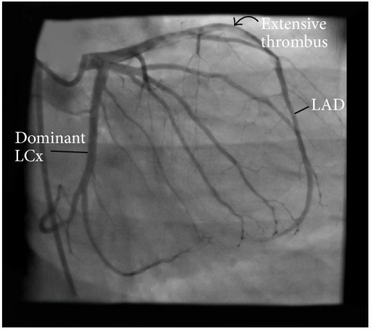

Imaging modalities used to evaluate the presence of coronary thrombi:[9]